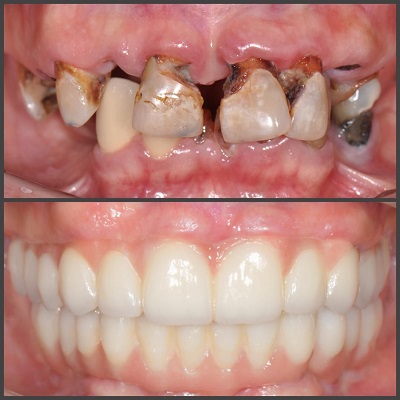

- تفسیر و شرح: یک دکتر لثه برتر باید بتواند نتایج آزمایشها و تصاویر درمانی را به شما توضیح دهد و درک برداری برای شما فراهم کند. آن ها باید به شما نشان دهند که چگونه درمانشان تأثیر داشته است و به شما اطمینان دهند که اعتماد به درمان آنها موجب بهبودی شما خواهد شد.